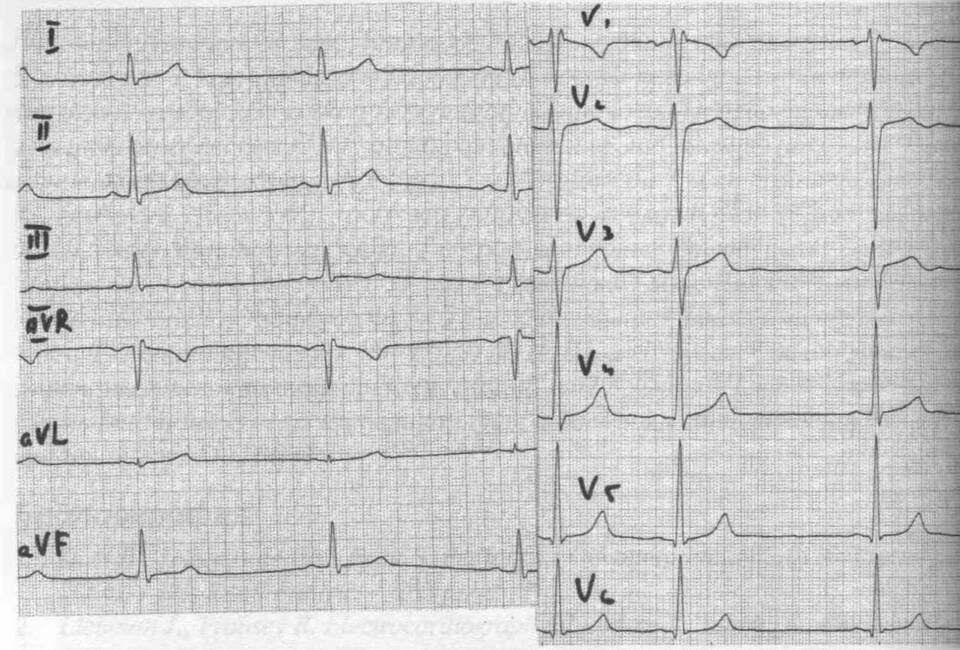

Нерегулярность сердечного ритма 6%, выявленная при электрокардиографическом исследовании, указывает на умеренные нарушения в работе проводящей системы сердца. Рассмотрим подробнее значение этого показателя.

- При наличии других отклонений на ЭКГ